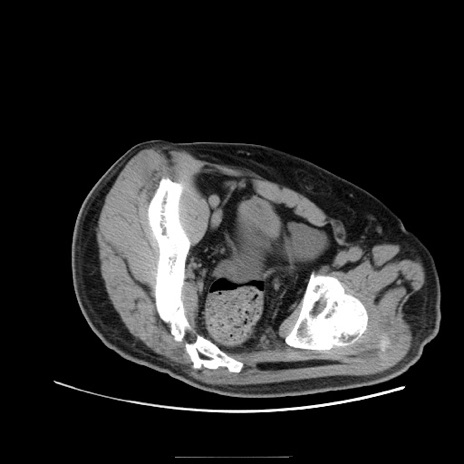

冠状断像

症例22(横断像)

【症例】50歳代男性

【主訴】腹痛

【現病歴】AVMからの被殻出血のため回復期リハ病棟入院中。 本日午後3時頃急に下腹部痛が出現した。

【既往歴】AVM、被殻出血、虫垂炎、高血圧

【身体所見】意識晴明、左半身不全麻痺、会話の理解は良好、36.5°C、腹部:膨隆、全体に板状硬、下腹部正中に圧痛点あり、反跳痛-、筋性防御不明、右下腹部にope scar

【データ】WBC 9400、CRP 0.06